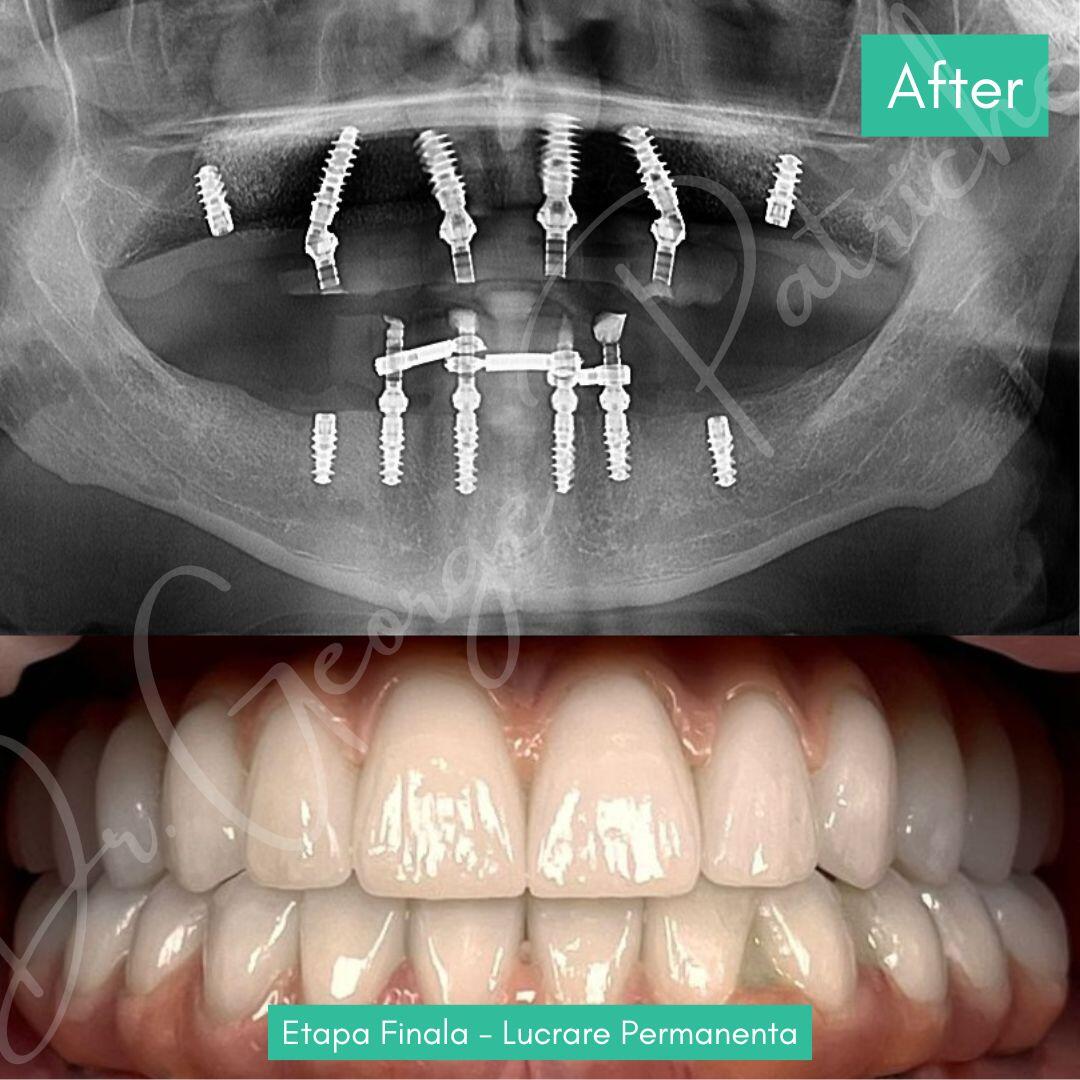

Before & After